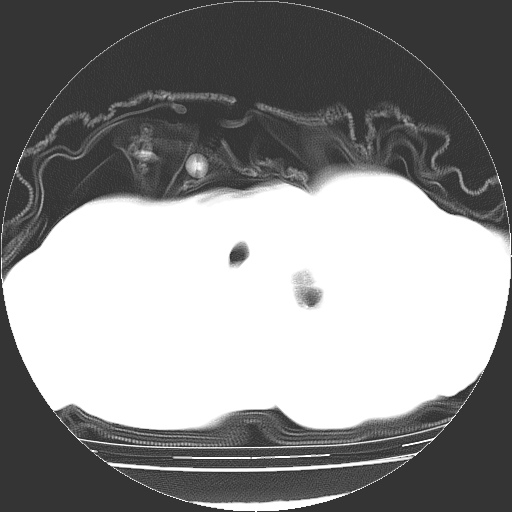

女,72岁,咳嗽、憋气一周,十年前曾患肺结核及胸膜结核。

1.右侧损毁肺伴胸膜钙化,2.左肺小结节灶,良性可能大,注意复查。3.肝脏左叶囊肿。4.先天性一侧肺不发育待出外(右侧胸廓无明显塌陷)。对比原片应该非常有帮助。

支持楼上,肝脏多发囊肿